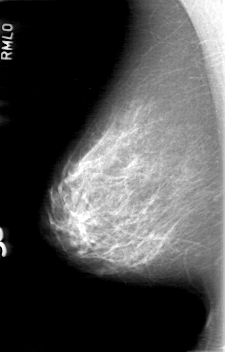

D_4058_1.RIGHT_MLO

RIGHT_CC LINES 5251 PIXELS_PER_LINE 3136 BITS_PER_PIXEL 12 RESOLUTION 43.5 NON_OVERLAY

RIGHT_MLO LINES 5266 PIXELS_PER_LINE 3361 BITS_PER_PIXEL 12 RESOLUTION 43.5 NON_OVERLAY